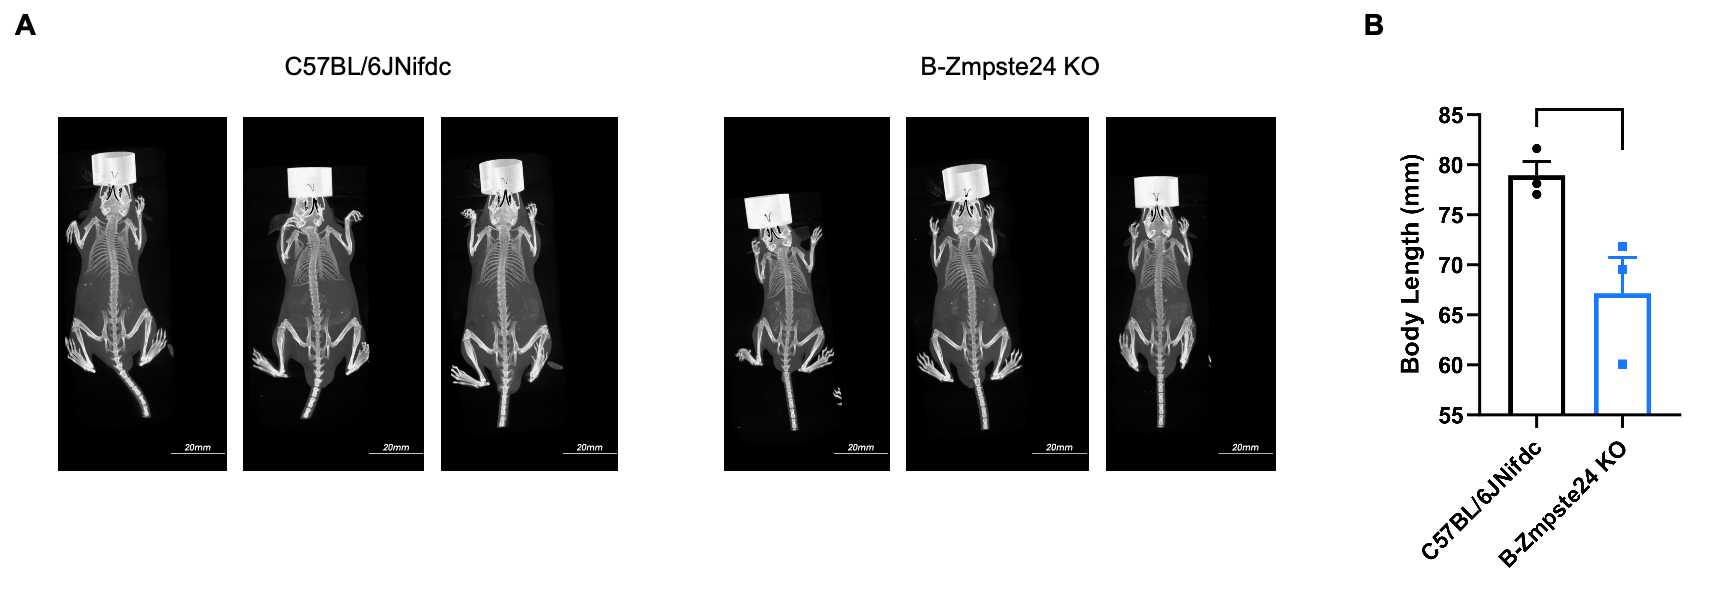

Whole-body micro-CT imaging of homozygous B-Zmpste24 KO mice. (A) Representative whole-body micro-CT images of mice wild-type C57BL/6JNifdc mice (n=3, male, 6-week-old) and homozygous B-Zmpste24 KO mice (n=3, male, 6-week-old). (B) Quantitative comparison of body length (from oral-nasal region to tail tip). Body size of homozygous B-Zmpste24 KO mice was smaller than wild-type C57BL/6JNifdc mice. Data are presented as mean ± SEM. *P < 0.05, **P < 0.01, ***P < 0.001. Scale bar = 20 mm.